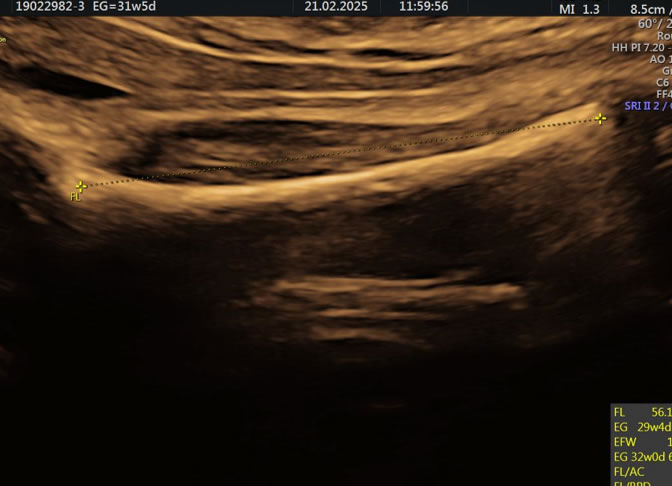

• Eco Doppler III Trimestre